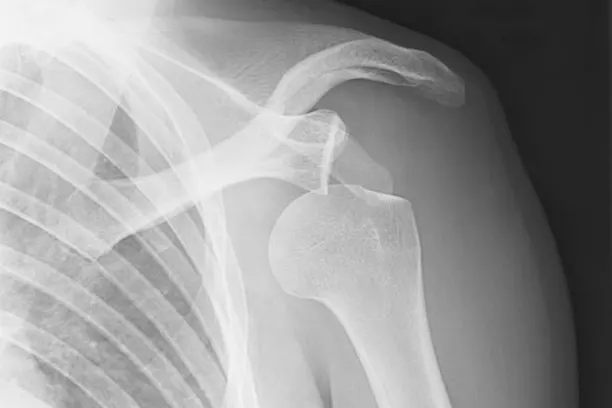

Closed Reduction Dislocation Major & Minior Surgeries

Closed reduction is a medical technique utilized to realign displaced bones without resorting to surgery. It is frequently employed in cases of dislocations, where a bone has been forced out of its usual position within a joint. The necessity for more extensive surgical procedures varies depending on the seriousness and characteristics of the dislocation. Closed reduction is a widely used and successful treatment for dislocations, although the requirement for additional surgeries is contingent upon individual circumstances, such as the extent of the injury and any accompanying complications. Rehabilitation is vital in attaining the best possible results and regaining full functionality of the affected joint.